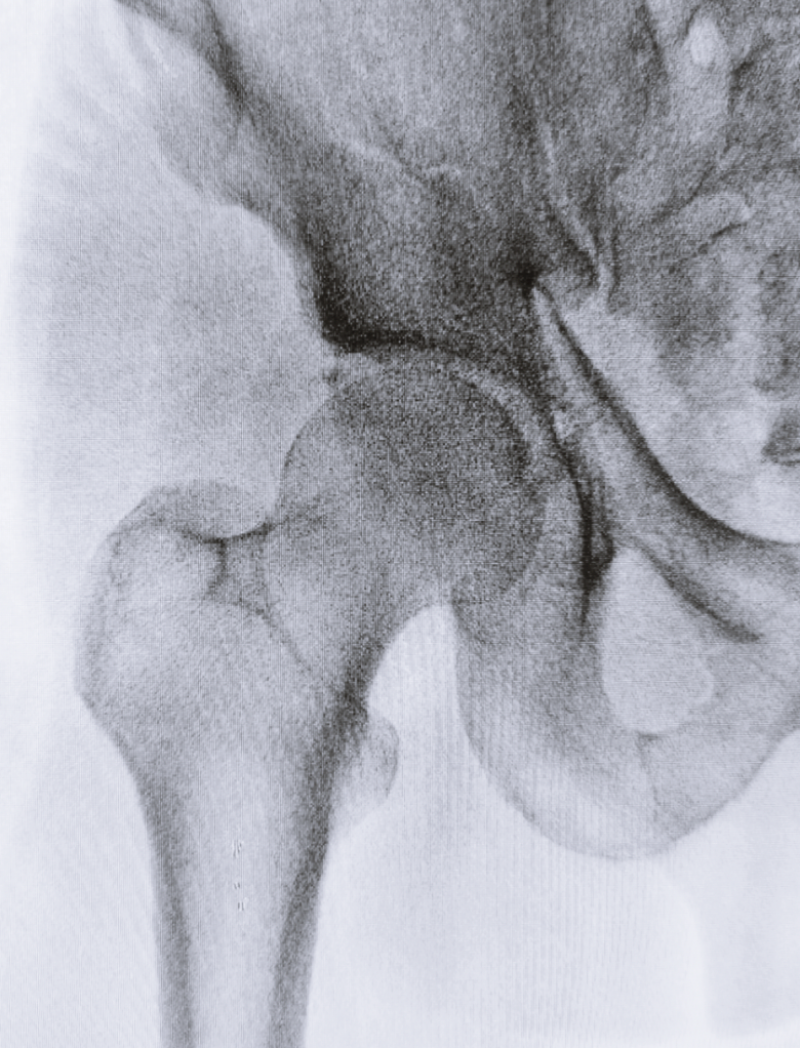

4. 고관절 골절

고관절 골절은 어떠한 외상으로 인해 대퇴골의 경부 또는 전자간부가 부러진 경우인데요. 상대적으로 뼈가 약한 노년층에서 그 발생빈도가 높습니다. 마찬가지로 고관절 골절이 일어나면 극심한 통증과 함께 움직임에 제한이 생기게 되므로, 나이가 있는 사람들의 경우 빠른 수술을 진행해야 합니다.